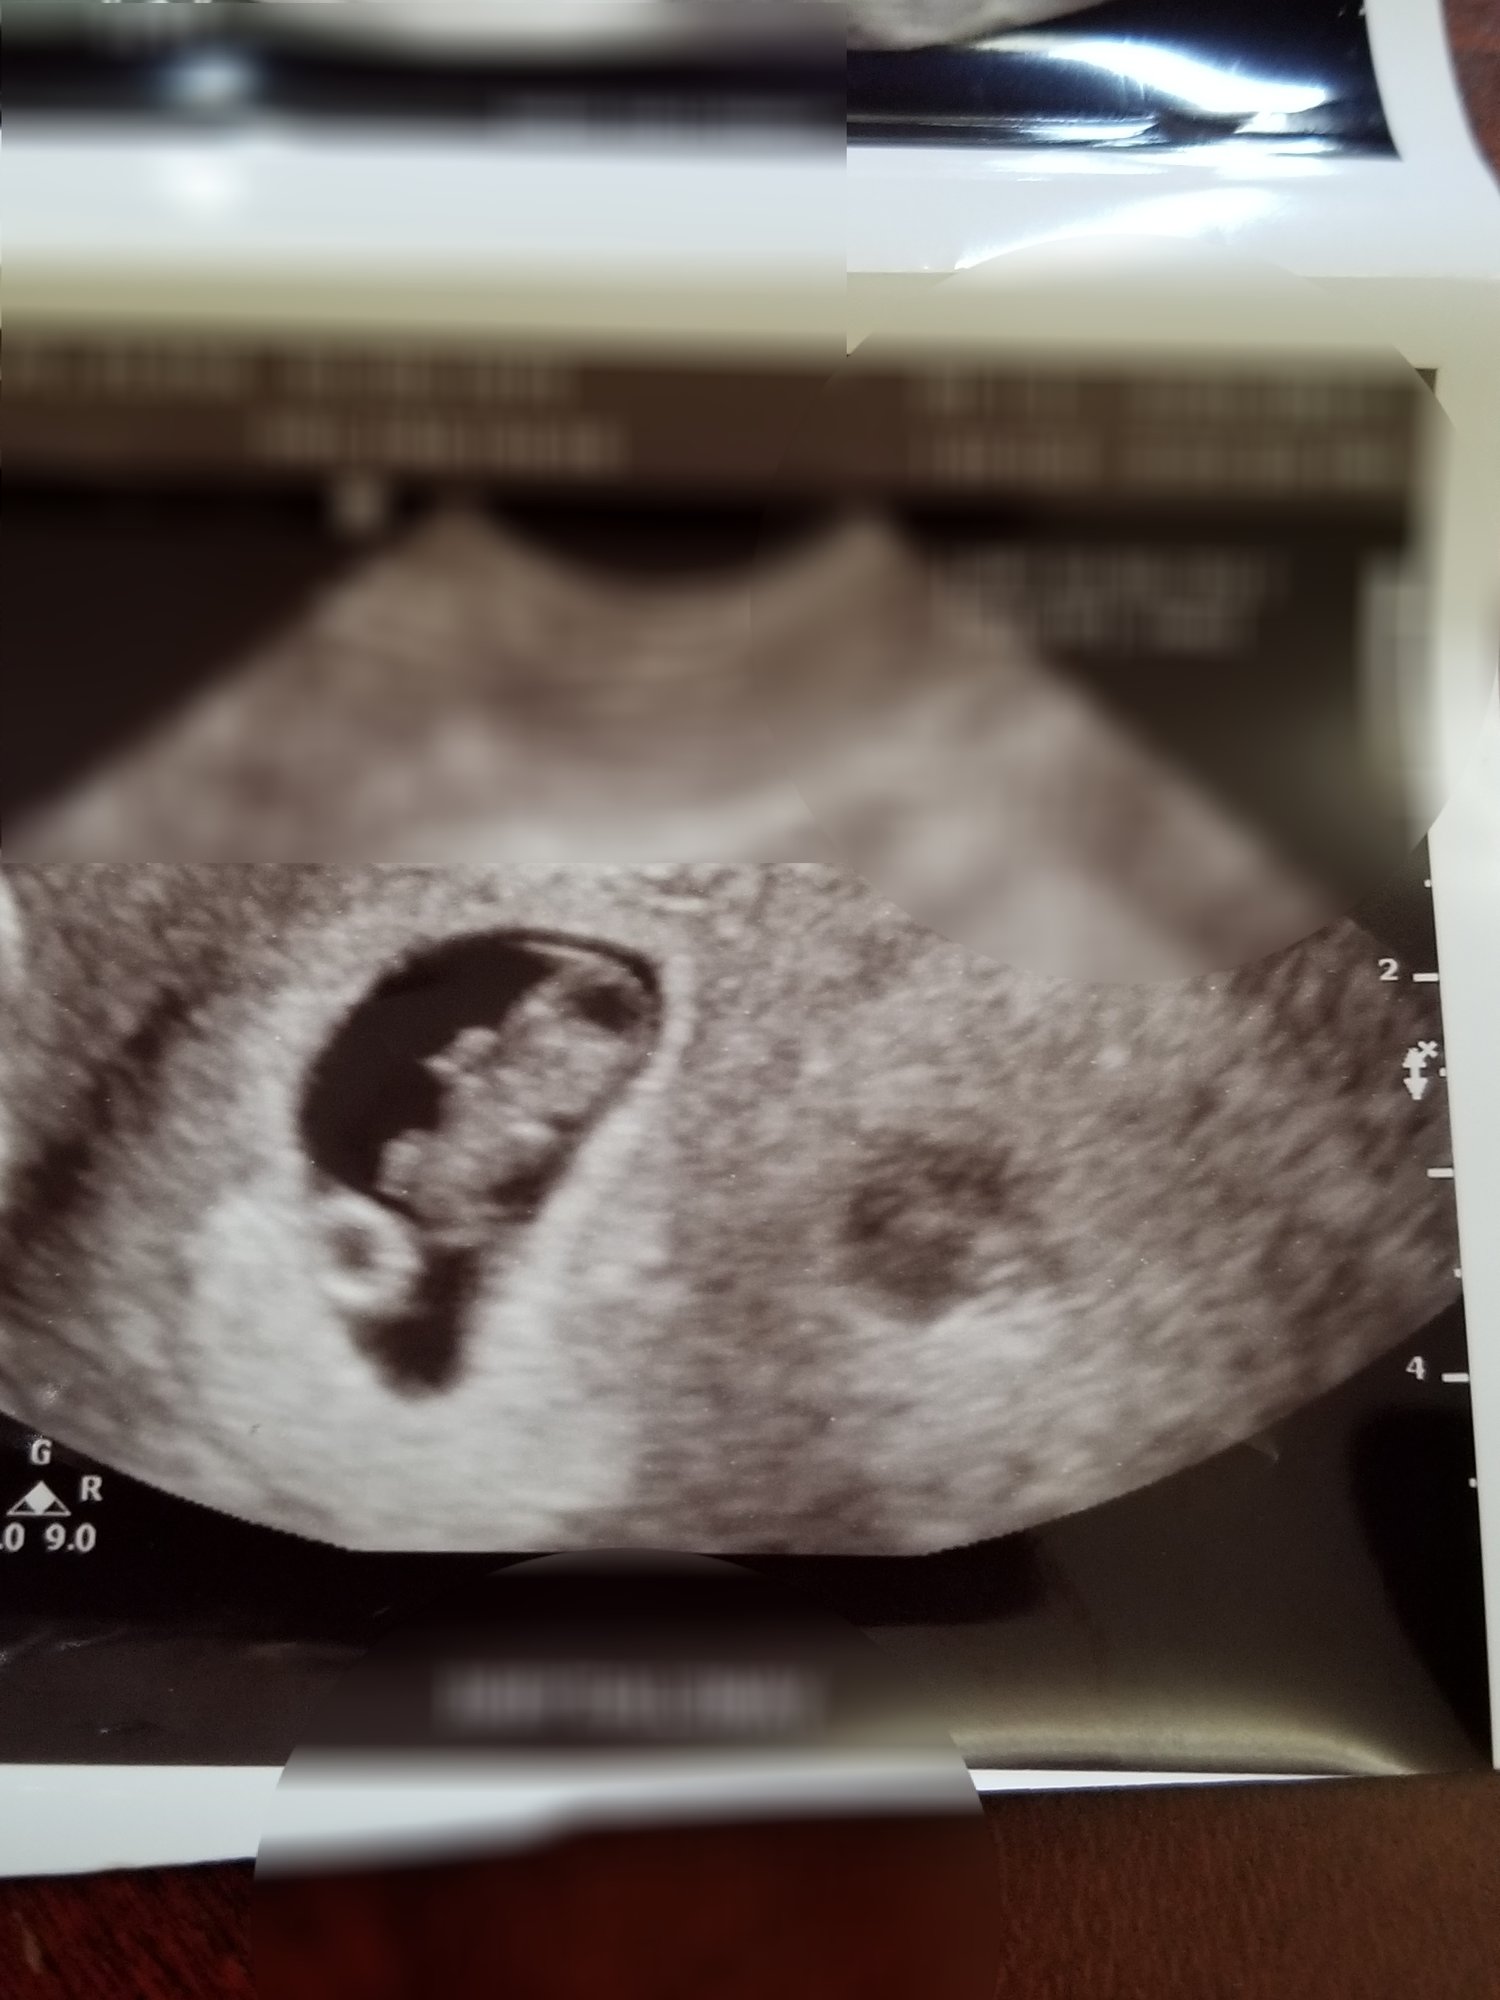

I had my third U/S on Friday. I was exactly 9 weeks. Baby measured right on track for 1/5 due date and had a heart rate of 182. My doctor was super pumped! You can even see baby's little arms and legs. Legs are to the left, head is to the right, little belly in the middle, and then a little arm sticking up. So cute!